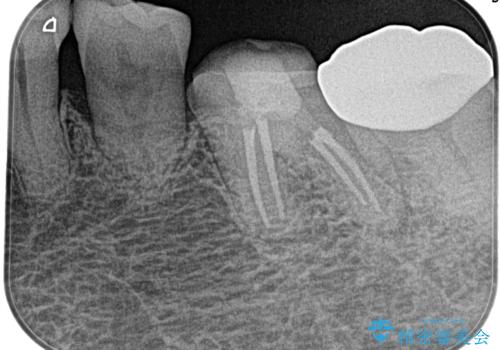

奥歯がズキズキ痛い 根管治療

- 冷たいもので強い痛みがあり、1週間前ぐらいからズキズキ痛いことを主訴に来院されました。

患歯に冷温刺激に対し20秒の持続痛と打診を認めたため、不可逆性歯髄炎の診断とし治療を行なっております。

- 精密根管治療(イニシャルケース,大臼歯):122,000円、ファイバーコア:22,000円費用は治療当時の料金となります

不可逆性歯髄炎と診断される場合は、経過観察を行なっても正常歯髄に戻る可能性は極めて低いため今回の処置のように抜髄の適応となります。